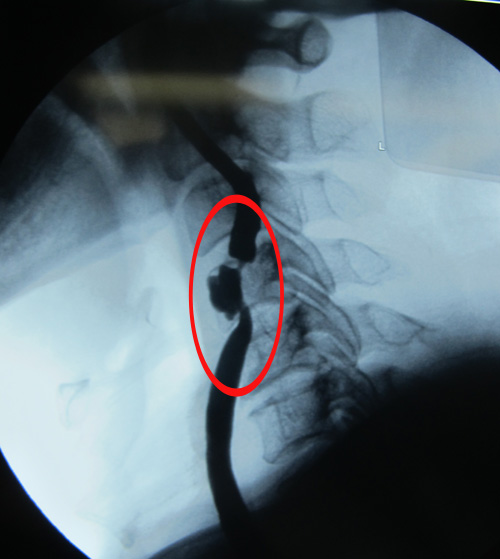

头颈CTA示:右侧颈内动脉近端闭塞,左侧颈总动脉远端及颈内动脉近端重度狭窄

颈部血管超声示:双侧颈动脉粥样斑块形成伴左侧颈动脉狭窄(重度)。

该患者为急性起病,既往脑梗塞病史13年,心肌梗塞病史1年。右侧颈内动脉近端闭塞,左侧颈总动脉远端及颈内动脉近端重度狭窄,均达到手术指征。患者无明确手术禁忌症,故采取手术治疗,去除病变,改善症状并预防中风发作。